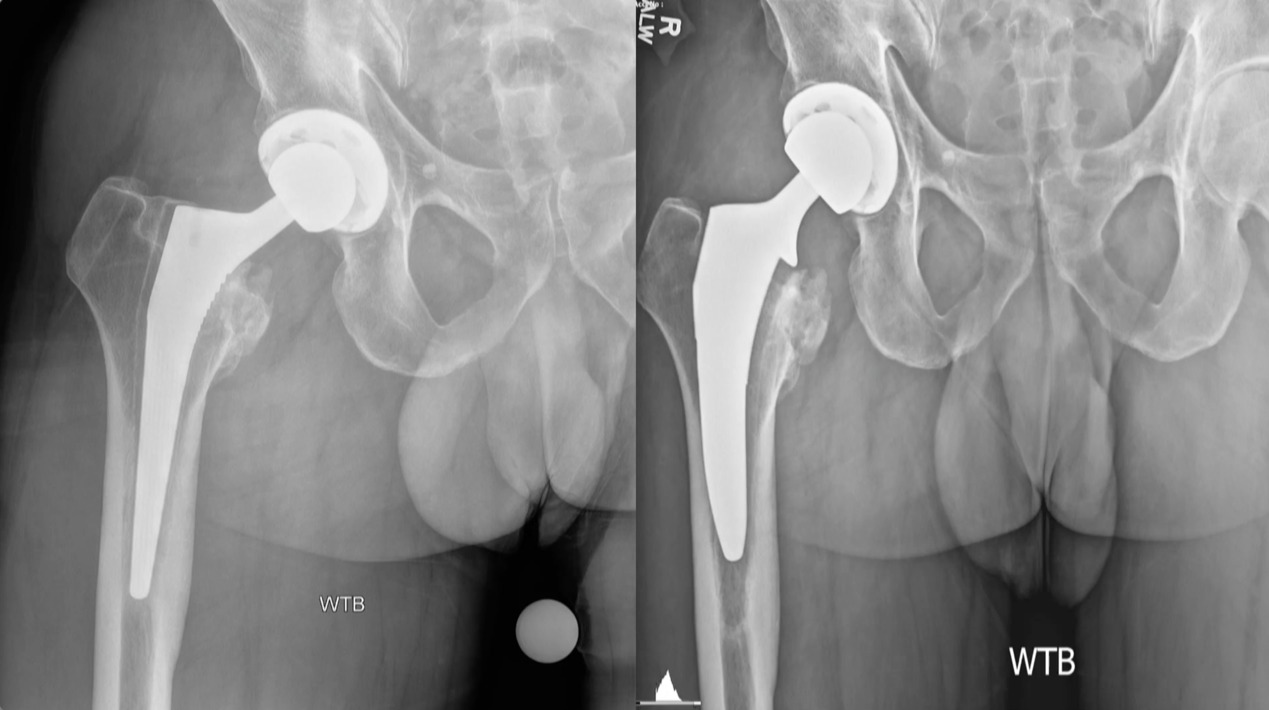

It’s just a couple quick cases that I feel are pretty ideal for the ASC. This is just a loose femoral stem here went in and actually revise this with a modern triple tapered stem. (Figure 4)

We’ve done this on quite a few cases and this is working really well, but you don’t have to use a primary stem, you can use a revision stem. But these loose components are ideal for the ASC setting. This was an ileus-psoas impingement. (Figure 5)